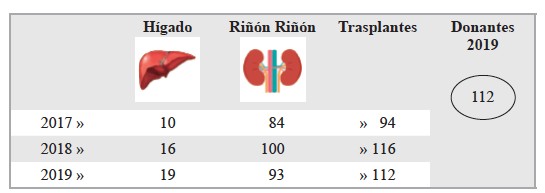

Julio César Núñez Villegas, Sergio Mauricio Rubel Cohen, Gabriel Alfredo Cavada Chacón, Laura Segovia González, Carlos Luis Matus Floody, Antonio Sa Cunha, Vilma Rodriguez, Rodrigo Abularach Cuellar